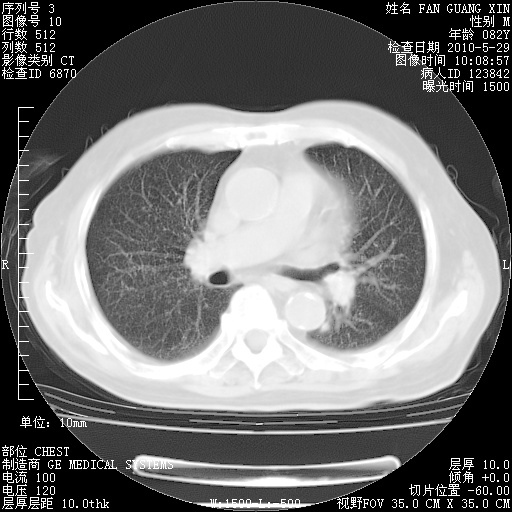

再治疗10天后的肺部CT

再治疗10天后的肺部CT 纵膈窗

阅读此次胸部CT,肺间质渗出性改变较入院时有吸收。目前从体温、白细胞、中性分叶明显增高,肯定存在细菌感染(发生医院感染哦,若无消化道及泌尿系统等感染的依据,肺部感染可能大)。若你院头孢哌酮舒巴坦钠耐药率较高,同意你的方案,若48小时体温仍高,可考虑使用碳青霉稀类抗菌药物,同时可予超声雾化、注意滴数时加大液体量。白蛋白33.30g/L较低哦,需加强营养等支持治疗。